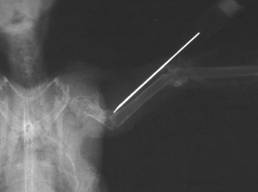

Radius fracture,

dislocated |

Radius fracture

after intramedullary pinning with a 0.4 mm

cannula |

The relatively frequent

radius fracture, which, if not treated, can lead to limited flight

ability, is pinned by using a 0.4 mm cannula, which is inserted into

the distal end of the fracture, exits through the radius head which

is palpable at the shoulder joint and is retrogradely pushed into

the proximal end of the fracture as far as just in front of the

elbow joint. The pin coming out at the shoulder joint is released 1

- 2 mm over the skin, and is protected with a small adhesive strip,